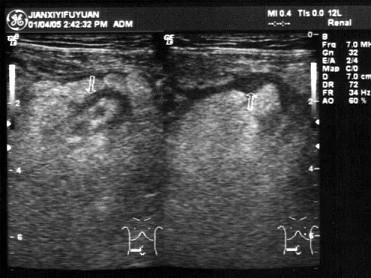

问题 患者男17岁,右下腹痛2天,体检:右下腹压痛及叩击痛(+)。B超检查如图所示,根据超声声像图,诊断为?(?)

选项 A.急性阑尾炎 B.回盲部肿瘤 C.肠套叠 D.肠穿孔 E.肠结核

答案 A